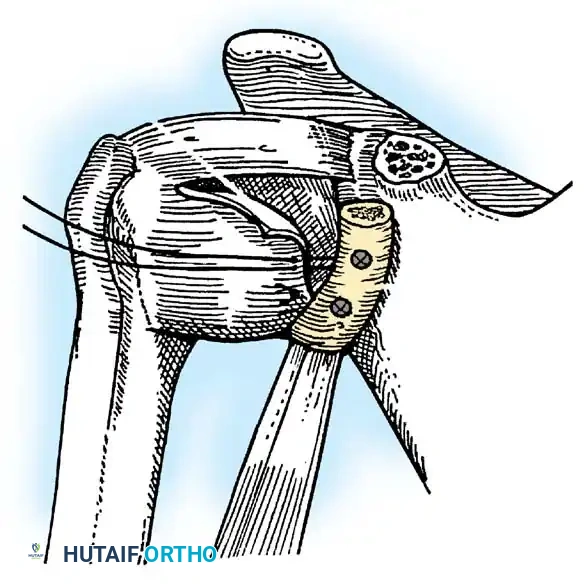

Glenoid Preparation and Labral Repair

The essential step in restoring stability is the anatomical reduction of the capsulolabral complex to a bleeding bone bed on the anterior glenoid rim.

- Debridement: The anterior glenoid neck is decorticated using a motorized burr, rasp, or osteotome to create a bleeding cancellous bed. This promotes robust biological healing of the repaired labrum.

- Mobilization: The scarred, medially displaced labrum (ALPSA lesion) must be fully mobilized using a periosteal elevator until the subscapularis muscle belly is visible anteriorly. The tissue must float freely to be shifted superiorly and laterally.

- Anchor Placement: Suture anchors (typically 3 to 4) are placed along the articular margin of the anteroinferior glenoid (from the 5:30 to 3:00 positions for a right shoulder). Anchors must be inserted at a 45-degree angle to the articular surface to maximize pullout strength and avoid joint penetration.